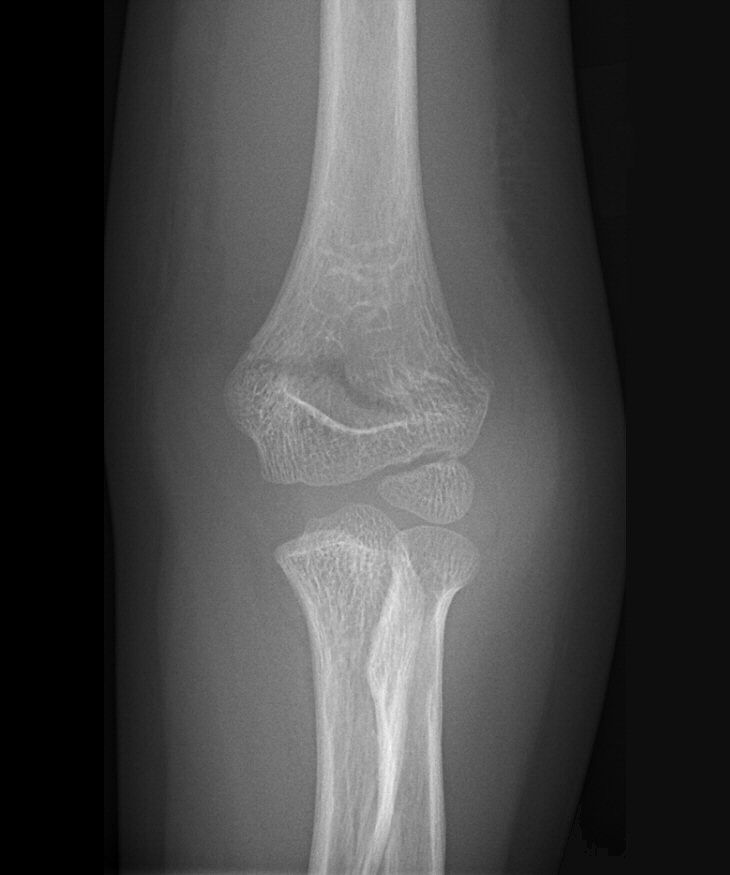

Fraktur på laterala humerusepikondylen, behandlades icke-kirurgiskt